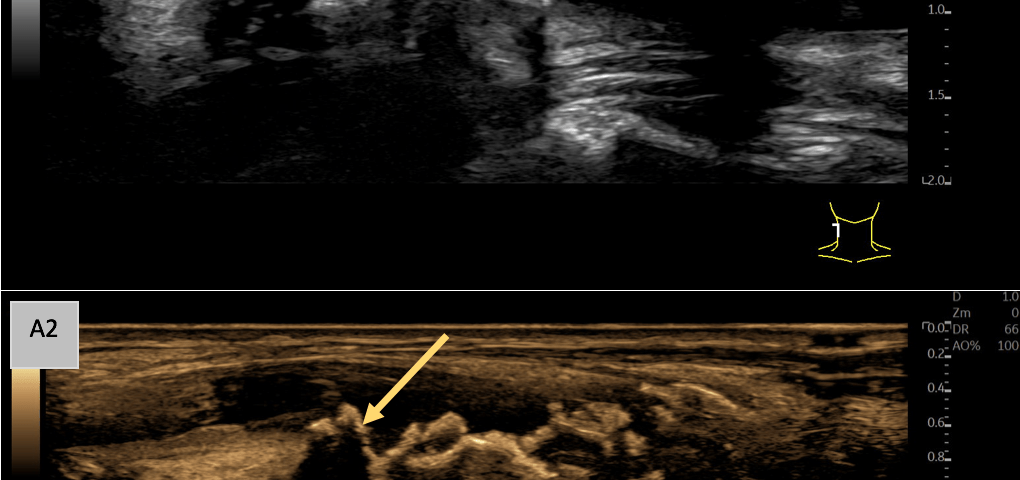

A: B-Mode imaging in the sagittal plane (A1) shows a markedly echogenic and inhomogeneous vessel wall of the common carotid artery with a thickened intima-media complex and irregular echogenic wall changes. Notably, multiple echogenic, wall-adherent formations with partial distal acoustic shadowing are observed (yellow arrow), indicative of significant plaque formation. Speckle Reduction Imaging (SRI) and Cross Beam techniques were employed to optimize the B-Mode image (A2), which is illustrated in sepia for enhanced visualization.